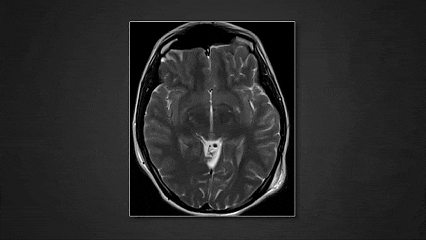

一名19岁的年轻女性以头痛为主诉就诊,影像学检查发现左侧小脑半球及桥小脑角区存在一枚肿瘤,测量大小约为五点三×四点零×三点五厘米。从影像上判断,肿瘤似乎起源于脑实质内部,并有明显的外生性生长趋势。病灶呈轻度强化,部分区域呈囊性改变,同时存在显著钙化。

术后影像